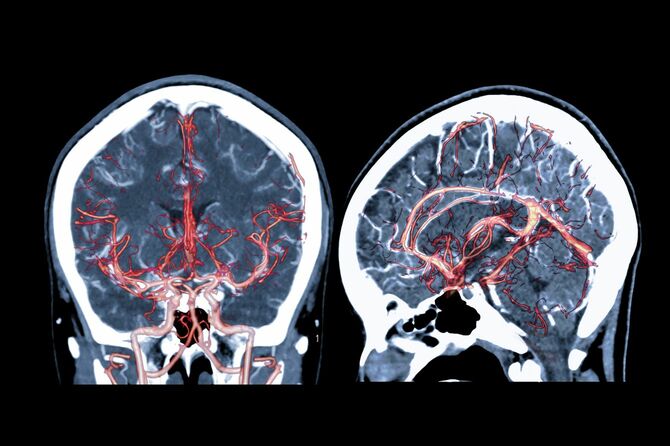

診察室で医師は、脳のCT画像を示しながら言った。

「脳出血です。右の瞳孔はすでに散大しており、左も開けば助からないでしょう。手術もかなりリスクが高いです。今手術しても、かなり重い障害が残る可能性が高いでしょう」

示された妻の脳のCT画像には、3分の1ほど血液で作られた真っ暗な空洞があり、素人目にも一目で「これはダメだな」と思わせるほどの説得力があった。

MRI・MRA画像で脳血管の損傷部位を確認

写真=iStock.com/mr.suphachai praserdumrongchai

※写真はイメージです

「『左頭頂葉皮質下出血』それが妻の疾患名でした。いわゆる脳卒中(脳出血)です。左脳の深部血管が破れ、すでに大量の血液が妻の脳を覆っていました。発症した原因は不明とのこと。妻は生まれつき脳の血管に奇形があり、それが破れた可能性があるそうです。発症時は生理で、貧血気味であったこと。また脳の静脈が閉塞しており、行き場をなくした血液が動脈へ負荷をかけた可能性があるとのことでした」

その言葉は、設楽さんを納得させるには、十分な答えだった。脳の3分の1ほどを覆うドス黒い出血の空洞を映し出したCT画像を見ながら、昔から妻に聞かされていた言葉が設楽さんの頭に浮かんでいた。